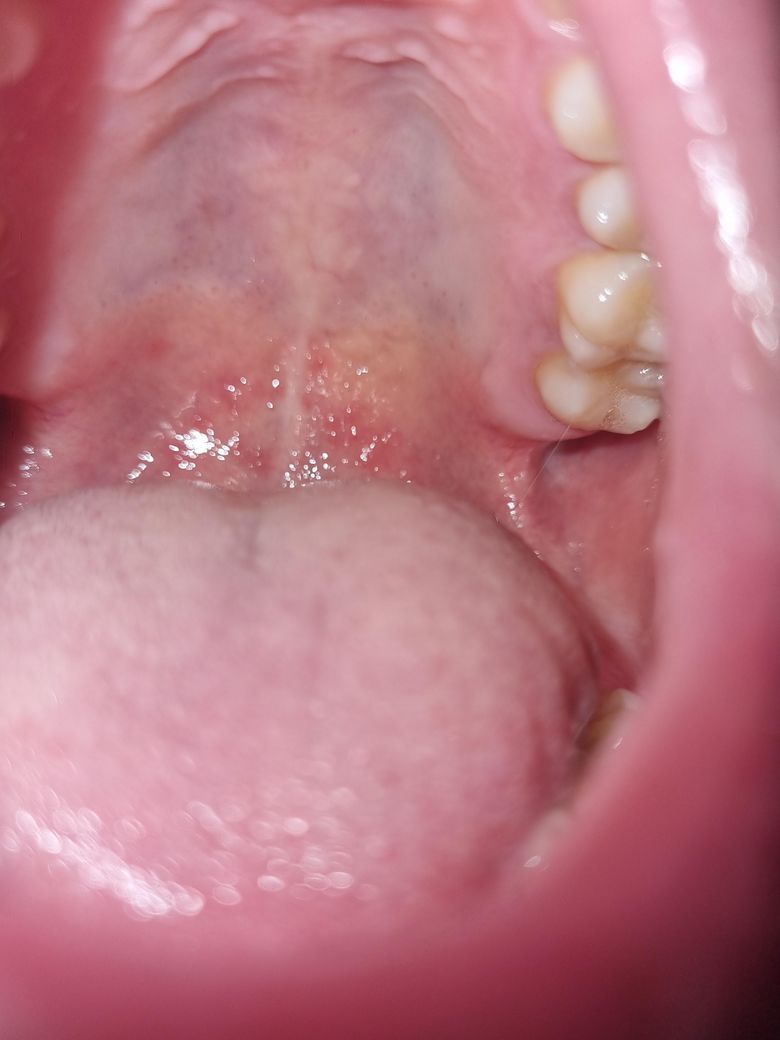

입천장에 빨간 수포 발생했는데 원인이 궁금합니다.

관계 중 구강성교도 했는데 후에 1시간 후? 입천장에 이물감이 느껴졌고, 이상하게 여겨 보니까 수포같이 올라와 있었습니다.. 여러가지 알아보니까

등 인거같은데, 일단 저는 이물감이 있고 통증은 딱히 없으며 열도 없구요. 입안에 입천장 저기 말고는 따로 난곳이 없습니다 입술주변도 없음.

하지만 목이 답답한 느낌이들게 부어있어요.

• 1번 째 사진